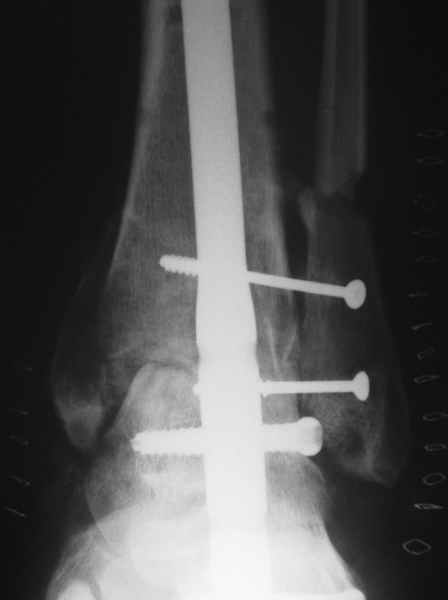

Michael Berenstein 24 Сентябрь 2004, 11:36

Nail arthrodesis for failed pilon fracture is good solution.

My example

Michael Berenstein